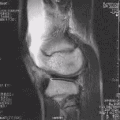

Imaging

MRI

Both anterior cruciate ligament (ACL) and posterior cruciate ligaments (PCL) are hypointense on both T1 and T2 weighted images of MRI. However, some high signal striations are often seen at the distal part of the ACL, making ACL higher intensity than PCL on MRI scans.[20]